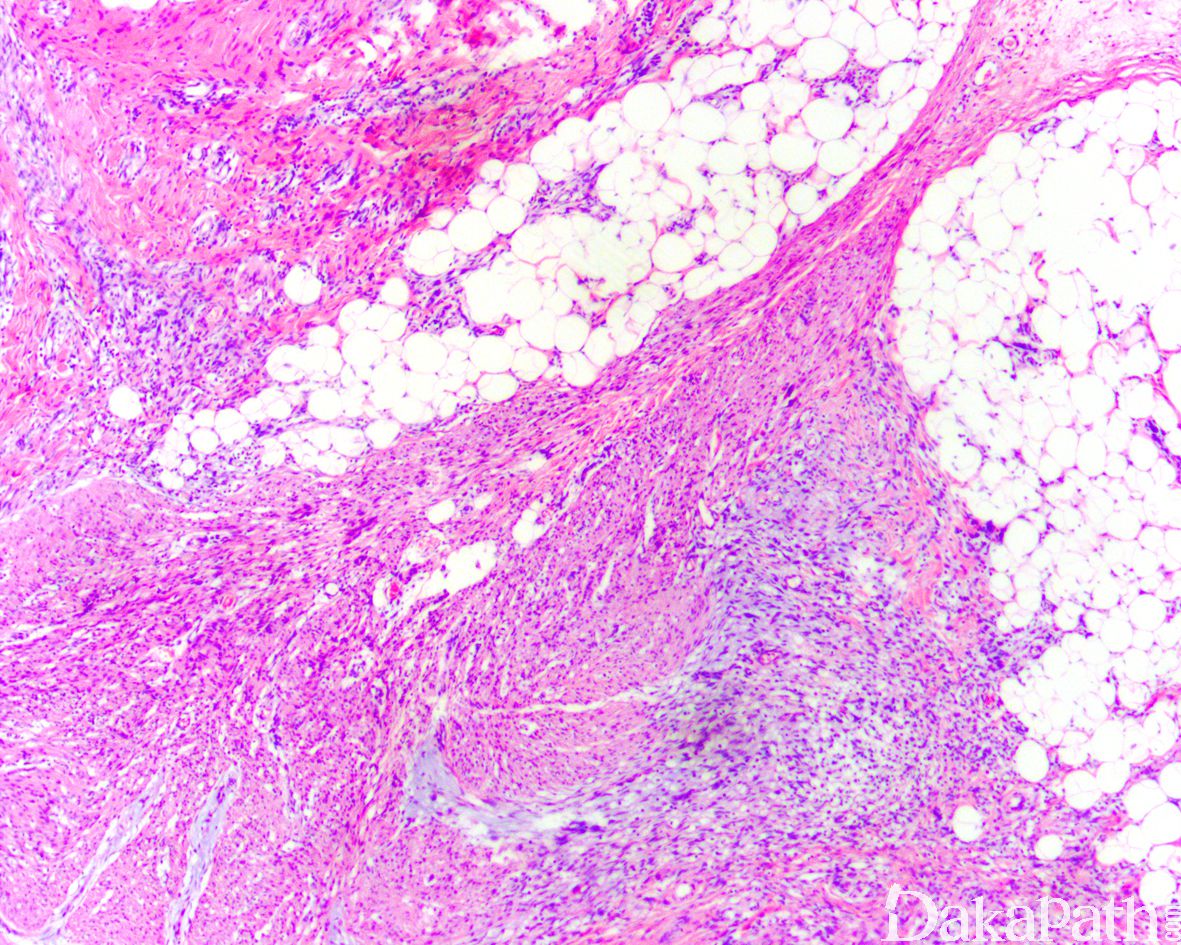

一种发生于婴儿的浅表性软组织肿瘤,镜下主要由三种成分构成包括:成熟的脂肪、呈梁状生长的纤维瘤病样梭形细胞以及结节状聚集的原始间叶性细胞。

镜下位于真皮深层或皮下,边界不清;由致密梭形细胞、原始间叶细胞和成熟脂肪组织组成,不同病例三者比例不同:

致密的纤维组织由比较成熟的纤维母细胞、肌纤维母细胞和胶原纤维组成,呈纵横交错的束状排列,常呈指状伸入脂肪组织内,组织学类似于纤维瘤病;部分区域可见梭形细胞之间成片的胶原化或瘢痕化以及多核巨细胞沉积,类似于乳腺的假血管瘤样增生或巨细胞纤维母细胞瘤样改变;

原始间叶组织呈结节状分布,由幼稚的短梭形、卵圆形或星状细胞排列成呈疏松的漩涡状、巢状或宽带状包被于富于血管的黏液性基质之间;